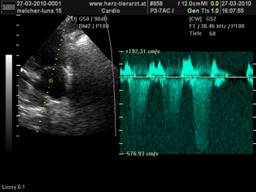

Der Herz-Ultraschall ist gerade in der Tiermedizin die zuverlässigste und aussagekräftigste Methode der Kardio-Diagnostik. Im Gegensatz zum Röntgen, welches nur die äußere Größe der Herzsilhouette beschreiben kann, ist es mit dem Ultraschall möglich zu unterscheiden, ob eine Herzvergrößerung durch eine krankhafte Muskelverdickung oder aber durch eine Herzüberdehnung bedingt ist. Der Ultraschall ermöglicht uns außerdem, direkt ins Innere des Organs zu blicken und jede einzelne der insgesamt vier Herzklappen darzustellen, sodass Klappen –Verengungen und –Verdickungen sowie undichte Klappen eindeutig erkennbar sind, was von enormer Wichtigkeit für die Wahl des richtigen Medikaments ist. Mit der hochmodernen Doppler-Sonographie werden schließlich noch die Stärken der einzelnen Blutströmungen gemessen, was für die endgültige Diagnose und für spätere Kontrollen von Bedeutung ist, um den Verlauf der Krankheit und den Therapie-Erfolg zu beurteilen.

Obwohl der Herz-Ultraschall die mit Abstand beste Untersuchung vom Herzen ermöglicht und beliebig oft wiederholbar ist, ohne den Patienten einer Strahlenbelastung auszusetzen, bleibt sie aufgrund der hohen Geräte-Anschaffungskosten und der nötigen jahrelangen Erfahrung des Untersuchers nur wenigen Spezialisten vorbehalten. |